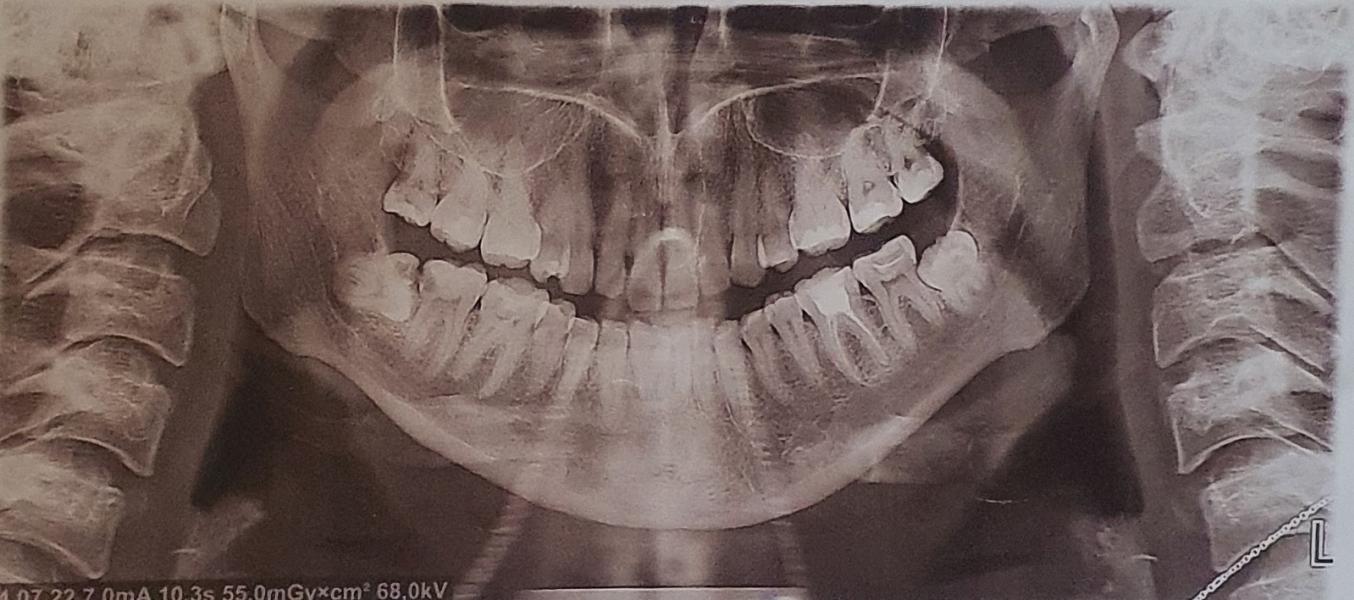

post image